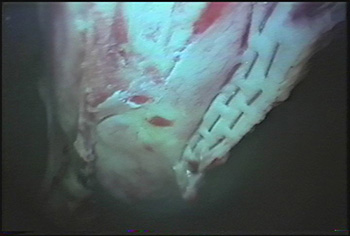

Horse with abnormal enlarged ovary

Intra-abdominal view of ovarian pedicle of the tumor that has been stapled for hemostasis before removal through the paralumbar incision.